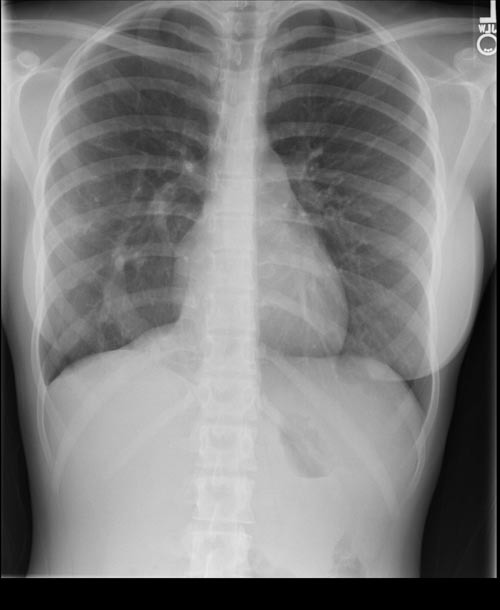

CLINICAL HISTORY:

36yo Male

Longstanding cough, increasing breathlessness.

No history of smoking

FINDINGS:

Lungs are hyperinflated with visible bullae formation in both lower zones suggesting severe emphysematous change. No pleural abnormalities demonstrated.

Heart size is normal. Normal appearances of the right hilum, the left hilum is bulky but unchanged from previous imaging 10 years ago. Mediastinal contours are normal.

IMPRESSION:

Severe emphysematous disease. Considering patient age consideration should be made to alpha-1-antitrypsin deficiency.

BACKGROUND:

Reduced or absent levels of A1AT results in unchecked activity of neutrophil elastase. This causes the elastase in respiratory structures to be degraded, this is typically more severe in the lower zones due to gravitational blood flow. Pathogenesis may also result in cirrhosis.

DIFFERENTIAL DIAGNOSIS:

FOLLOW UP: